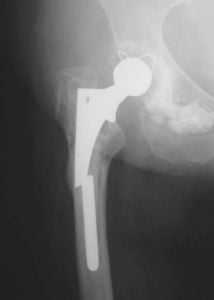

Дислокация бедренного компонента на рентгене.

Стрелками указаны зоны инфекционного воспаления, именно так они выглядят на рентгене.